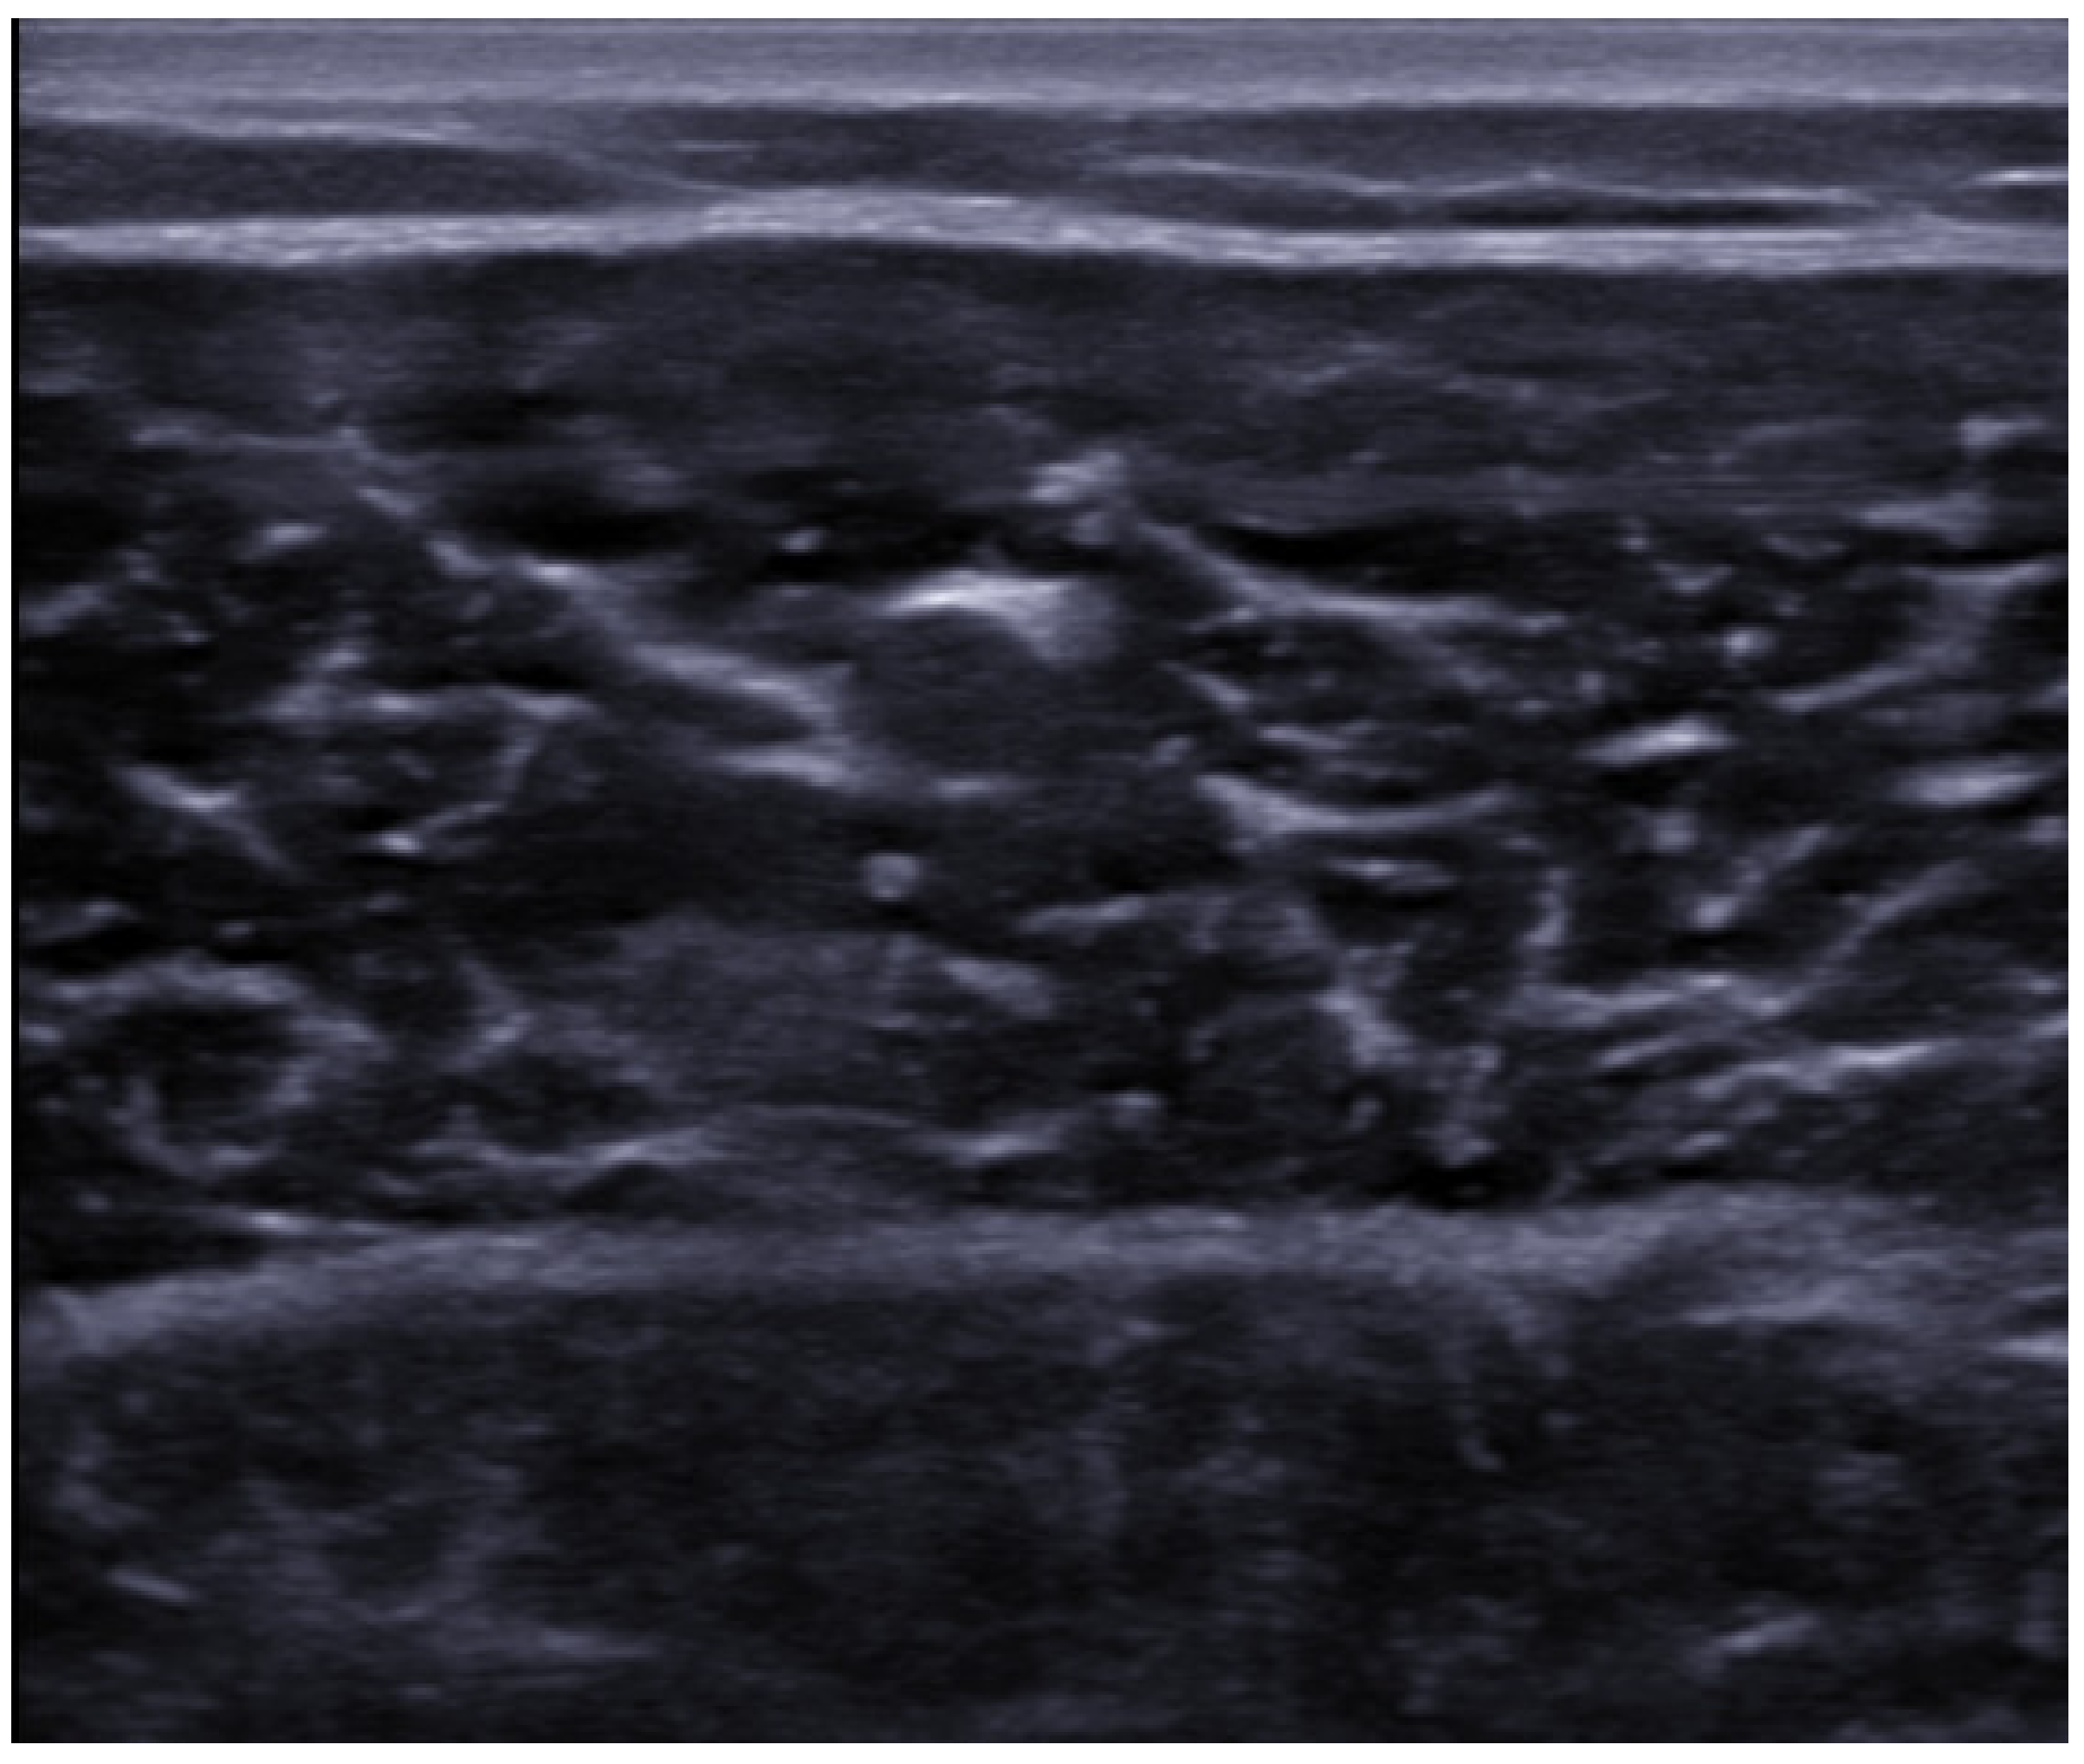

5. Ultrasound Findings of the Muscle Lesions

| Grade I | “<20% cross-sectional area.” | “Minimal elongations with less than 5% of muscle involved.” | “Normal, or focal/general areas of increased echogenicity +/− peri-fascial fluid.” | “Normal appearance; focal or general increased echogenicity with no architectural distortion.” |

| Grade II | “20–50% cross-sectional area.” | “5–50% muscle involvement, partial muscle rupture, demonstrable hypo or an echoic gap, with “bell clapper” sign.” | “Discontinuity of muscle fibers in echogenic perimyseal striae; hypervascularity around disrupted muscle fibers; intramuscular fluid collection; partial detachment of adjacent fascia or aponeurosis.” | “Discontinuous muscle fibers; disruption site is hypervascularized and altered in echogenicity; no perimyseal striation adjacent to the MTJ.” |

| Grade III | “>50% cross-sectional area.” | “Complete tear of muscle or fascia, with extravasation of collection away from injured part of muscle.” | “Complete myotendinous or osteotendinous avulsion; complete discontinuity of muscle fibers and associated hematoma; “bell clapper” sign.” | “Complete discontinuity of muscle fibers; hematoma and retraction of the muscle ends.” |